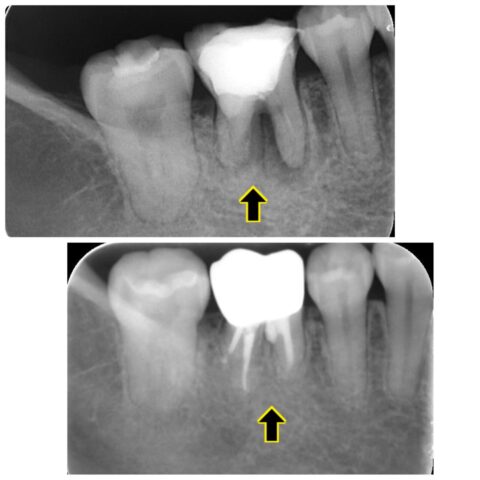

レントゲンで根の股の部分に歯質がなく、パーフォレーションがおきています。

それが原因で根尖病変ができ、骨が溶けてしまっているのでレントゲンで黒く映ります。

パーフォレーションが原因で根の分岐部に根尖病変がありましたがそれも回復しています✨